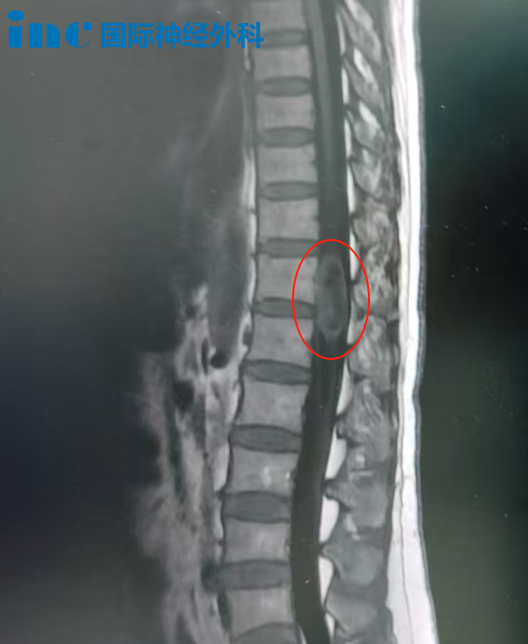

影像

示范手術(shù)在蘇州大學(xué)附屬第四醫(yī)院成功開展。吳先生的病灶位于大腦腳中腦腹側(cè)面,緊鄰腳間窩,解剖位置極為復(fù)雜:

1、運(yùn)動(dòng)功能風(fēng)險(xiǎn):大腦腳內(nèi)含下行運(yùn)動(dòng)纖維,若損傷可導(dǎo)致對(duì)側(cè)肢體偏癱;

2、顱神經(jīng)風(fēng)險(xiǎn):動(dòng)眼神經(jīng)自腳間窩發(fā)出,術(shù)中牽拉或熱損傷可能導(dǎo)致瞳孔散大、復(fù)視及眼瞼下垂;

3、操作挑戰(zhàn):病變位置深在,手術(shù)通道狹長(zhǎng)受限,對(duì)器械操控精度要求極高。